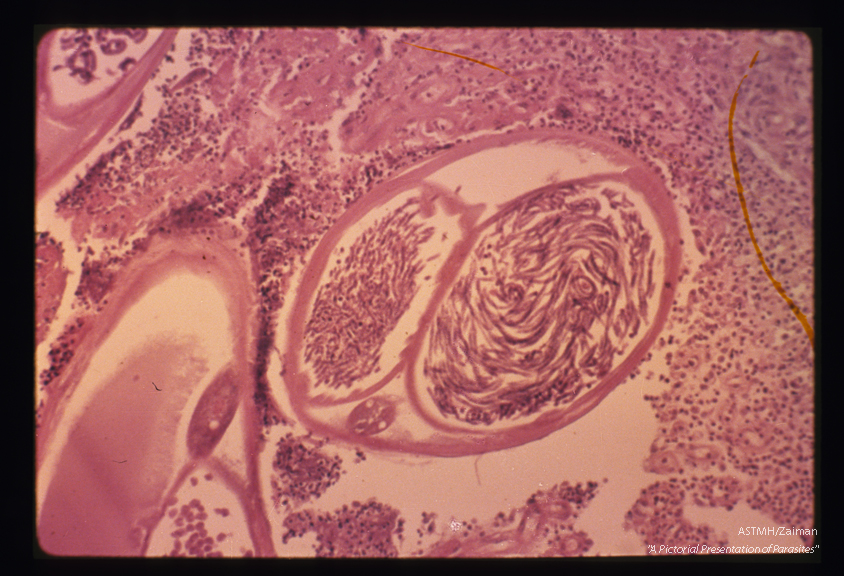

In this section, the microfilariae in the central parasite appear as graceful curves.

Onchocerca volvulus

Description: In this section, the microfilariae in the central parasite appear as graceful curves.